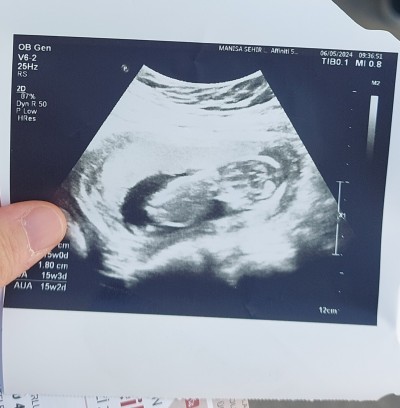

Merhaba güzel anneler 16 hafta gebeyim ulturason 15 haftalik cinsiyet tahmininde bulunabilir misiniz?

Birsey demek zor çok küçük birsey belli b olmuyor . Hayirla kucağınıza alın  banada Dua edin ikinci çocuğum olsun diye:*)